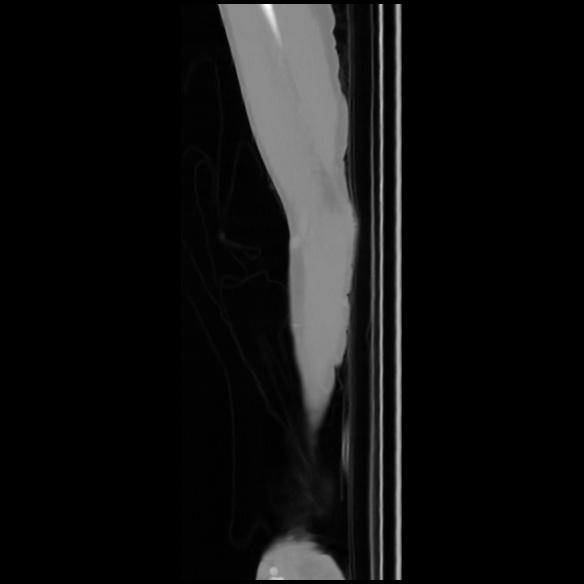

7 CUERPO,CE,Sagittal,3.000,CUERPO,Sagittal,